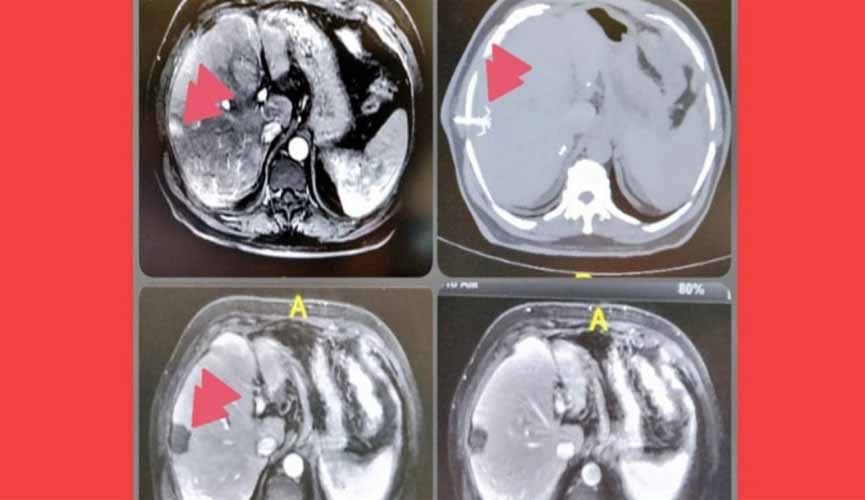

Chamada de ablação, a técnica utiliza radiação micro-ondas para "torrar" as células cancerígenas